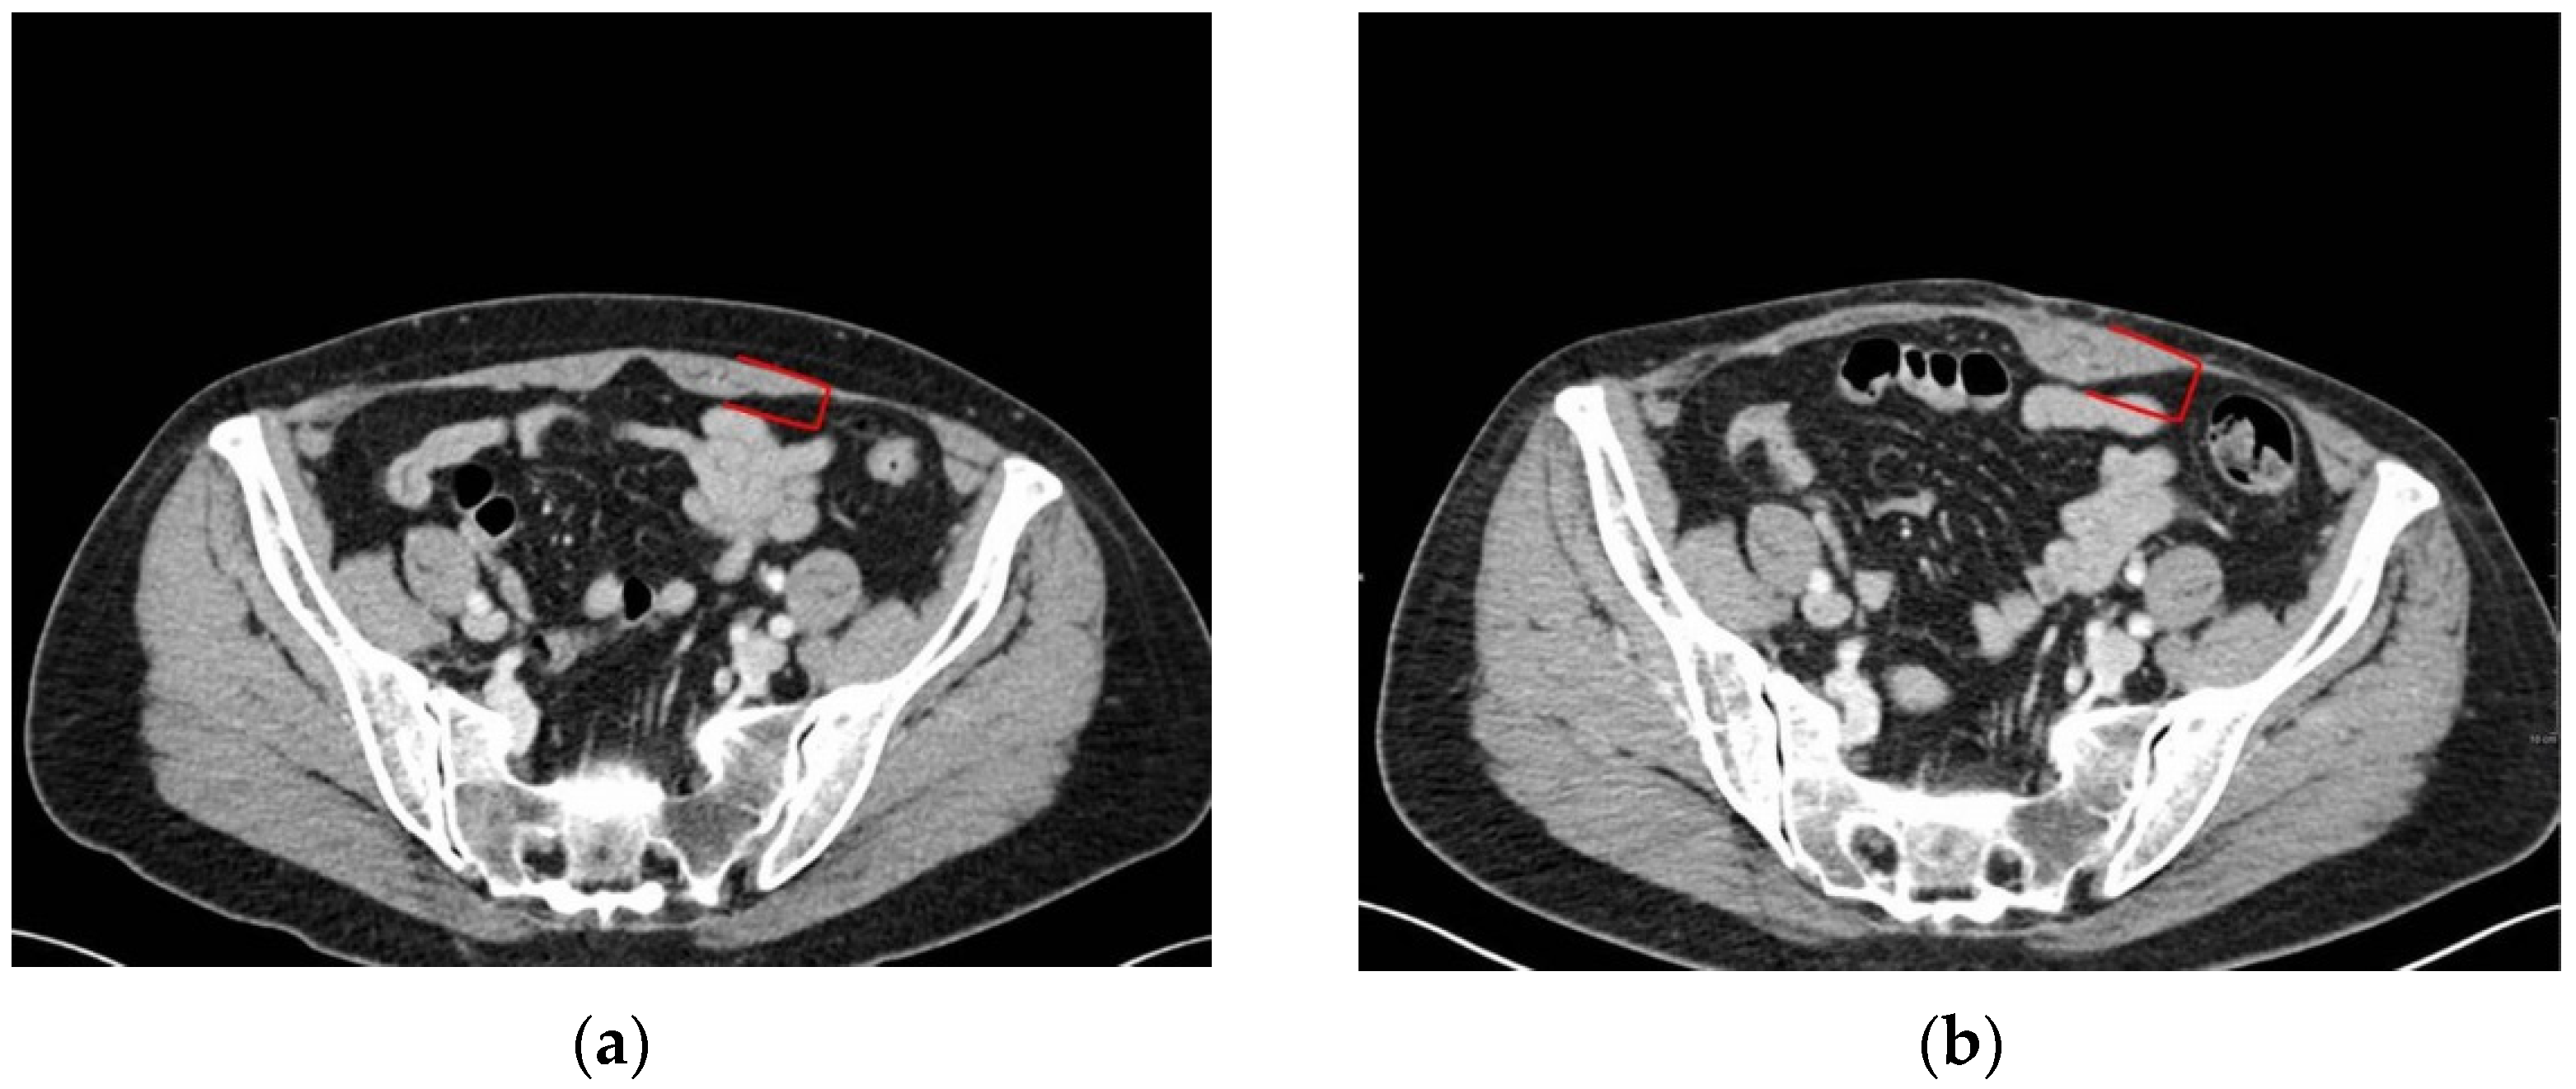

3.2. Muscle Quality Assessment